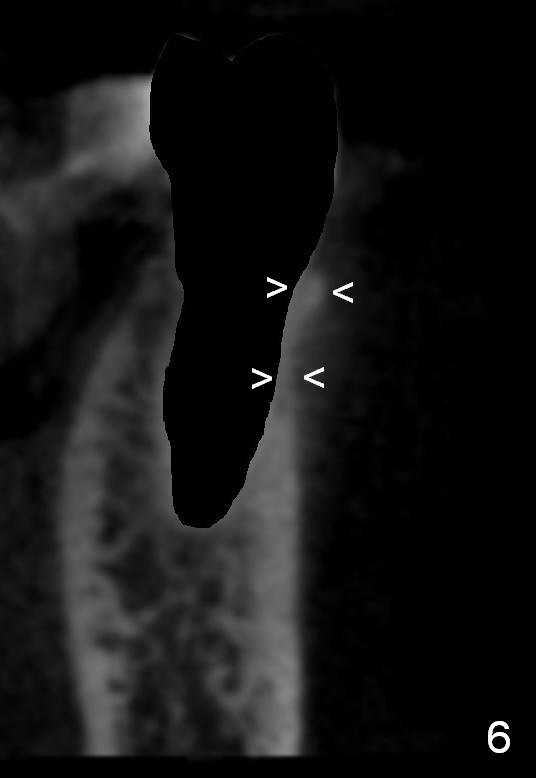

A 56-year-old man has poor dentition (Fig.1).  The tooth #20 fractures (not shown) after root canal therapy (Fig.2).  A 4.5x14 mm bone-level implant is planned (Fig.3).